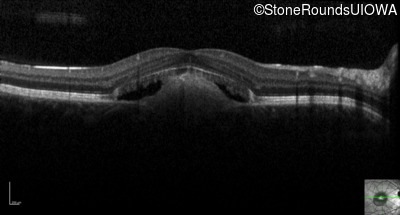

Optical Coherence Tomography - Right - 20/40 +2 sc

Exemplar / OCT Stack